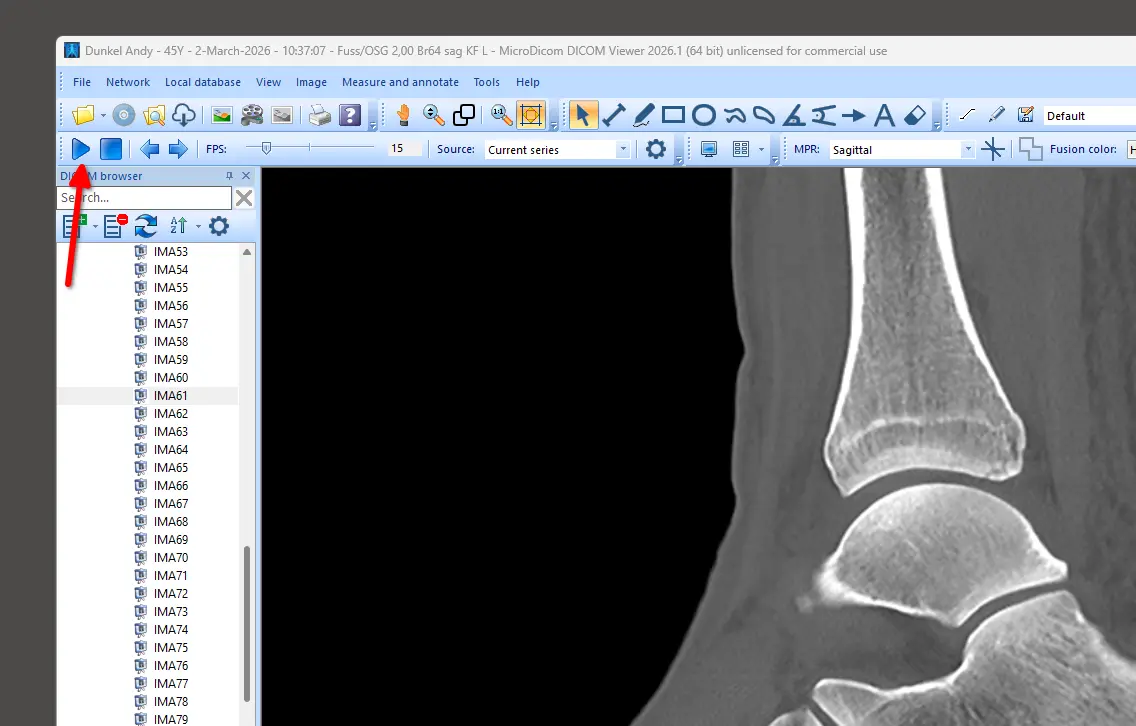

Beim Ct können wir den Play-Button drücken und so die Animation anschauen und an den Stellen stoppen und etwas erkennen oder nicht.